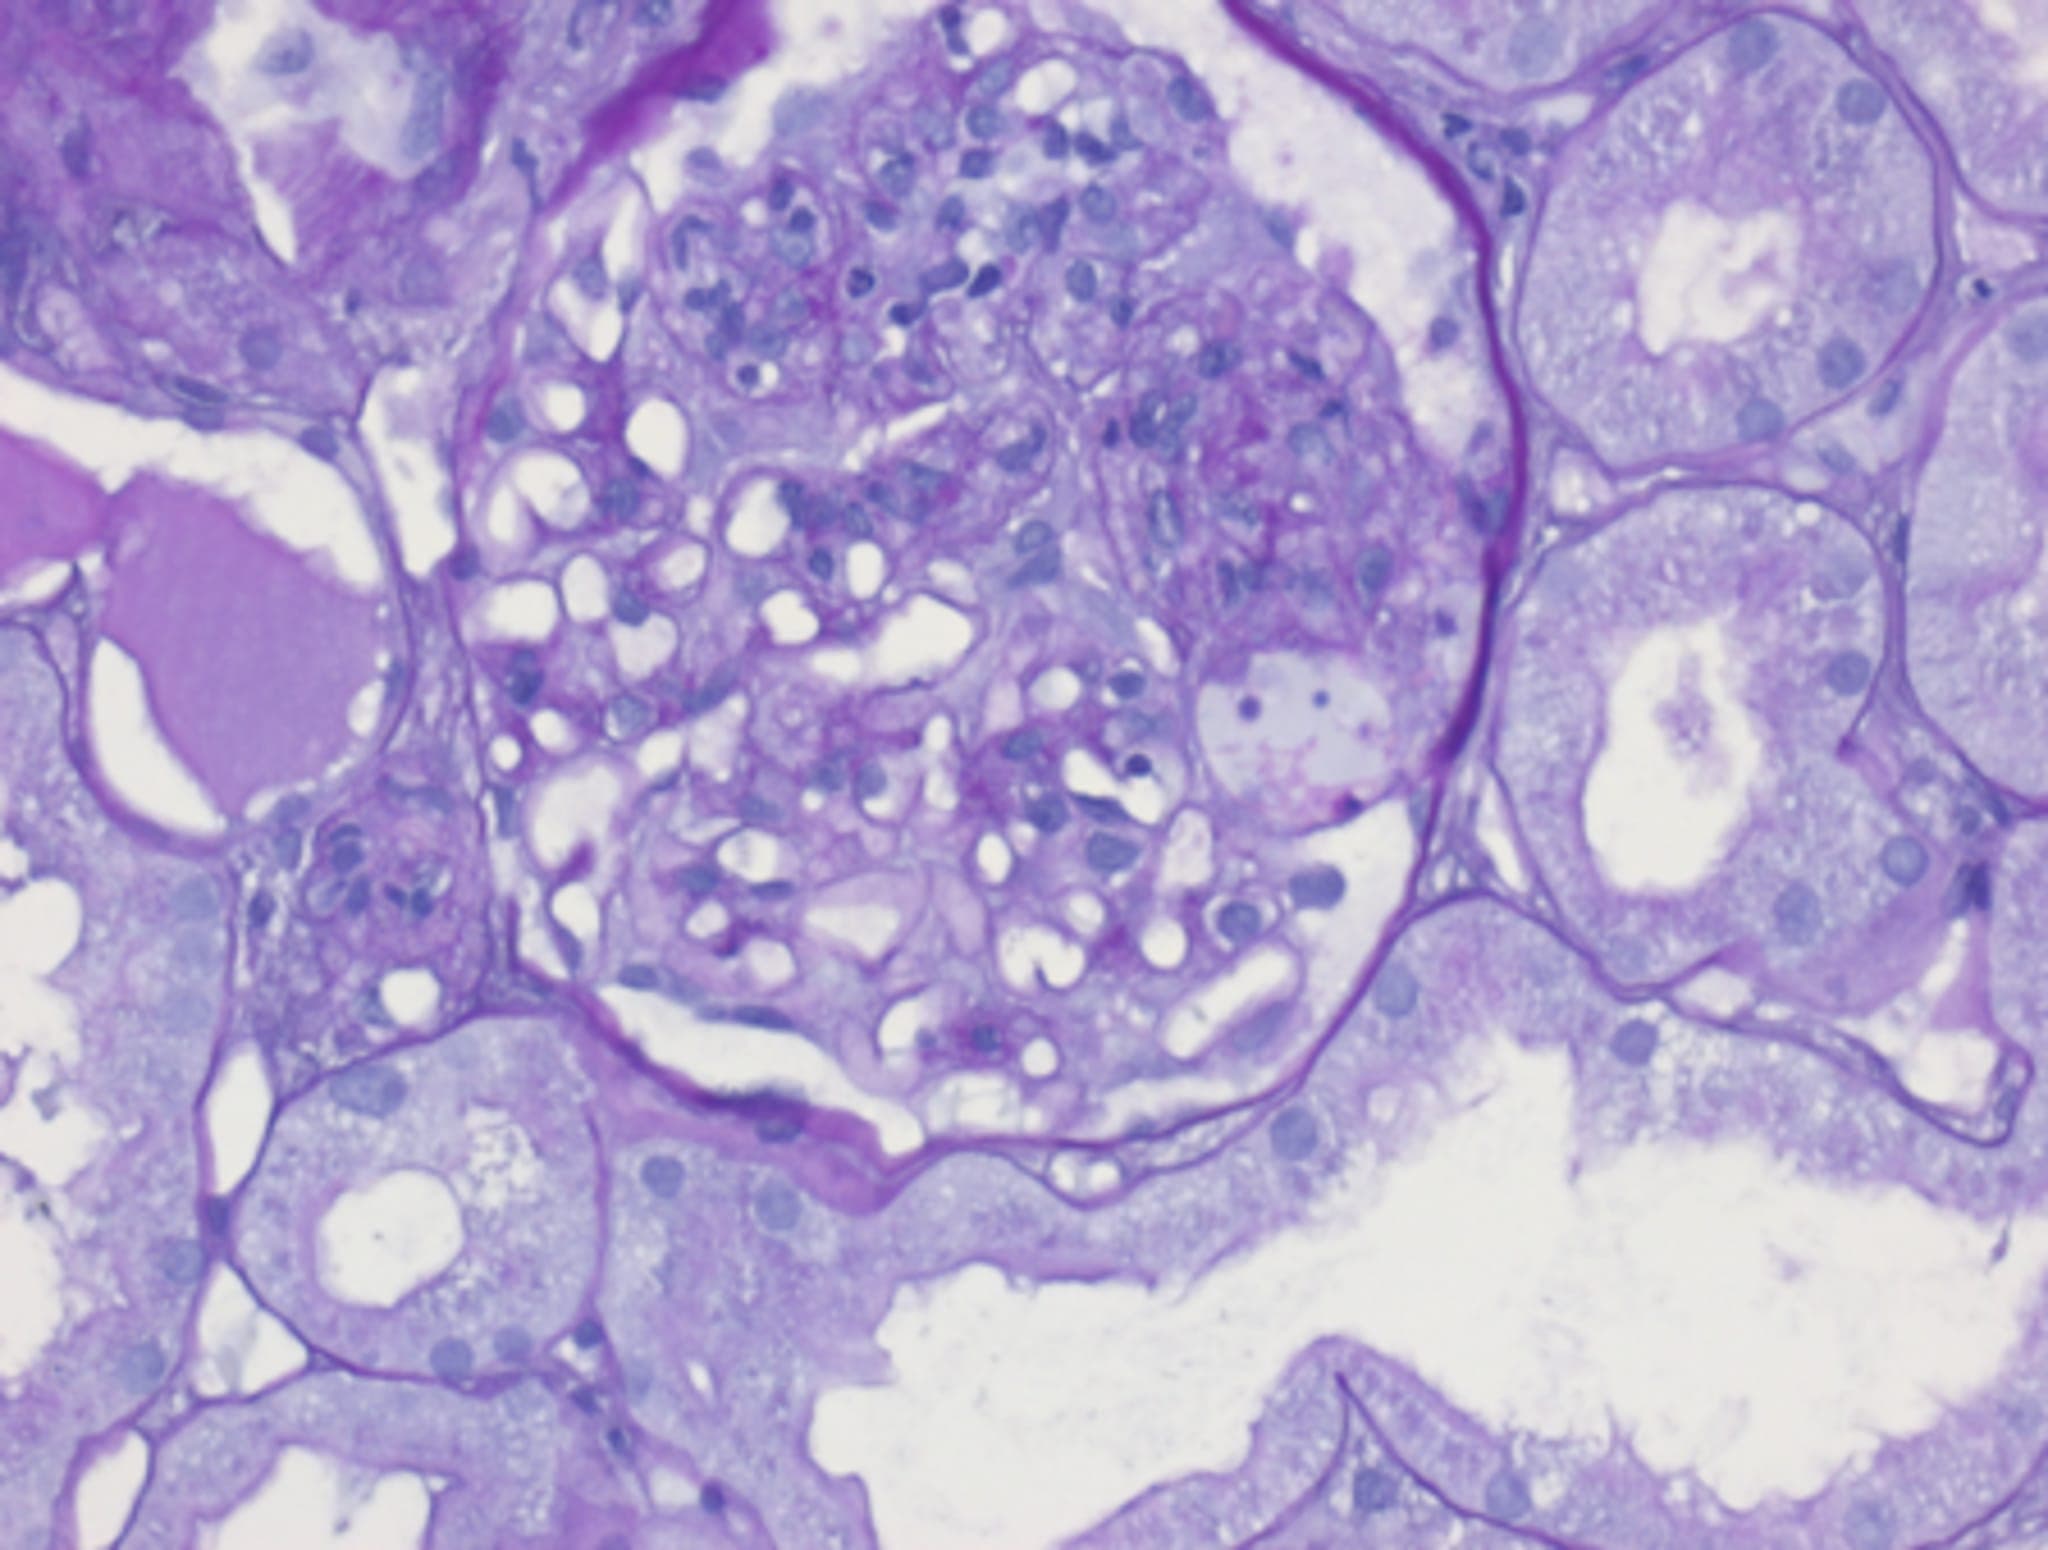

Schließlich liegen die Ergebnisse der Nierenbiopsie vor und bringen die entscheidenden Hinweise:

Intrakapillär proliferative und angedeutet auch exsudative Immunkomplex-Glomerulonephritis, a.e. Nierenbeteiligung bei IgA Vaskulitis mit zusätzlich a.e. infekt-assoziierter glomerulärer Nephropathie (GN)